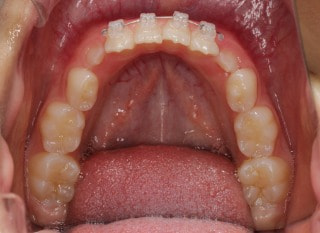

小児期第一段階

終了時